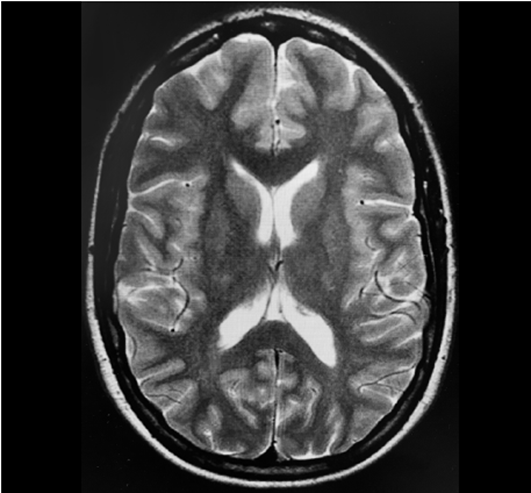

En el último estudio de resonancia magnética realizado en febrero de 2017 no se observó evidencia de tubérculos sub-corticales o subependimarios, los cuales son propios de la enfermedad (Figura 1). La paciente no había tenido crisis epilépticas desde 2014 y estuvo en tratamiento con lacosamida 250 mg dos veces al día durante todo el embarazo. Presentó tres episodios de migraña tensional con remisión espontánea durante el embarazo. La paciente ingresó al hospital en 2019 con ruptura prematura de membranas en la semana 31 de gestación y se indicó parto por cesárea debido a mala tolerancia fetal. El período mínimo establecido de ayuno fue de seis horas antes del procedimiento, después de una comida ligera. Los exámenes de sangre no mostraron ninguna alteración significativa. Ante la ausencia de hipertensión intracraneal y con base en los estudios imagenológicos previos, se administró anestesia con la técnica combinada espinal-epidural (TCEE) sin ninguna novedad. Tras ubicar el espacio epidural al nivel de L3-L4 con una aguja Tuohy calibre 18 se administraron 9 mg de bupivacaína hiperbárica al 0.5% más 20 microgramos de fentanilo utilizando una aguja Whitacre calibre 27. La posición del catéter epidural fue a 10 mm. No hubo complicaciones intraoperatorias y tampoco durante el período postoperatorio temprano.

A las 24 horas, la paciente presentó hipoestesia facial y braquial del lado izquierdo y cefalea hemicraneal del lado izquierdo, sin ningún otro signo neurológico. Se ordenó una resonancia de urgencia, en la cual se observó un tumor sangrante de inicio reciente en el lóbulo frontal derecho, sin efecto de masa. Se realizó una resonancia en 3D para un diagnóstico más preciso y una descripción anatómica del tumor (Figura 2). La paciente se diagnosticó con glioblastoma multiforme y se dio de alta a los 15 días de su ingreso con parestesia residual de la mano izquierda y programación para neurocirugía electiva. Posteriormente, la paciente se sometió a resección macroscópica total de todos los tumores visibles, seguida de ciclos subsiguientes de radioterapia y controles por oncología.